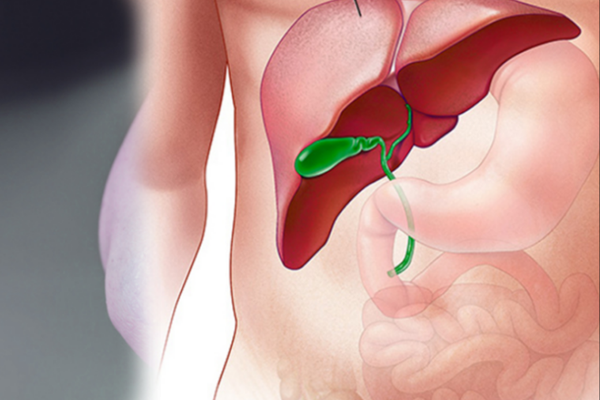

Dr. Jain specialises in sophisticated laparoscopic methods, providing minimally invasive alternatives to typical open surgery.

Dr. Jain specializes in the diagnosis and treatment of problems affecting the rectum, anus, and colon, including piles, fissures, and fistulas. He delivers compassionate and effective therapy.